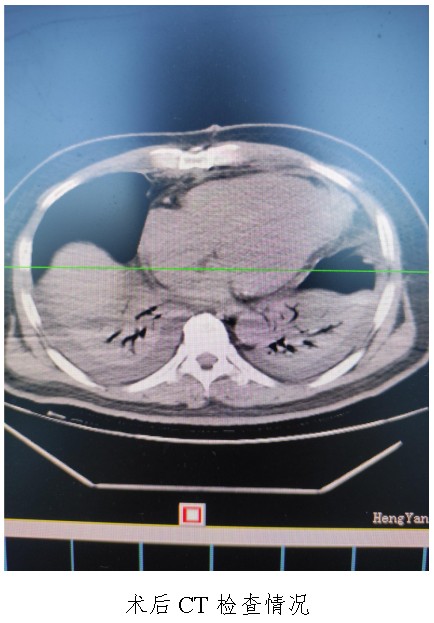

10月18日,50歲的孟先生因反復(fù)胸悶氣促一周,夜間不能平臥來衡陽市中心醫(yī)院心胸外科就診,經(jīng)心臟超聲檢查提示左心室前壁中下段及心尖部巨大室壁瘤,66×57mm,最薄處約3mm?;颊哂卸嗄晏悄虿〔∈?,既往有無癥狀心肌梗死病史,曾行PCI治療。入科后,廖金文主任、屈云劍副主任組織心內(nèi)、麻醉、體外循環(huán)、重癥醫(yī)學(xué)科對(duì)病人病情進(jìn)行了多學(xué)科討論,一致認(rèn)為手術(shù)是治療該病例的唯一手段。經(jīng)過充分的術(shù)前準(zhǔn)備,10月24日,心臟外科團(tuán)隊(duì)給患者實(shí)施了左心室室壁瘤切除加左心室修補(bǔ)成型手術(shù),手術(shù)順利,術(shù)后經(jīng)過精心的治療管理,患者恢復(fù)良好,康復(fù)出院。該病例的手術(shù)成功,不僅是術(shù)中及手術(shù)團(tuán)隊(duì)智慧的結(jié)晶,也是多學(xué)科合作的結(jié)果,展示了衡陽市中心醫(yī)院處理復(fù)雜危重患者的能力。